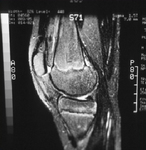

Tunnel view of osteochondritis dissecans

From the collection of H. Chambers, MD